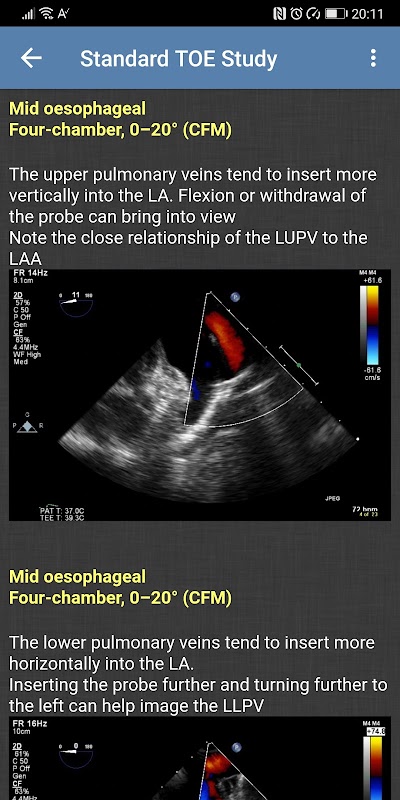

- Standard-TOE-Studie